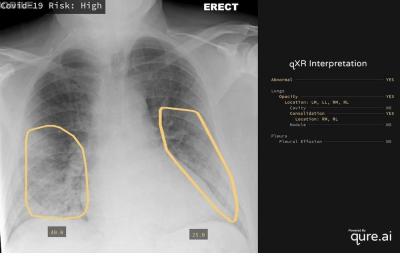

अच्छी खबर यह है कि झारखंड के कोडरमा के एक युवक ने एक आर्टिफिशियल इंटेलिजेंस (एआई) तकनीक का आविष्कार किया है जो सीने के एक्स-रे की मदद से महज 30 सेकंड में कोरोना के लक्षणों का पता लगा सकती है।

खास बात यह है कि अंकित और उनके सहयोगियों द्वारा विकसित इस सॉफ्टवेयर को रेडियोलॉजिस्ट की आवश्यकता नहीं है। इस सॉफ्टवेयर का उपयोग अमेरिका, इंग्लैंड, फ्रांस, इटली सहित दुनिया के 20 से अधिक देशों में किया जा रहा है।

जिन अस्पतालों में एक्स-रे रिपोर्ट आने में दिनों और हफ्तों का समय लगता है, वही रिपोर्ट अब इस सॉफ्टवेयर की मदद से कुछ ही मिनटों में आ रही है। जो डॉक्टर पहले दिन 25 से 30 एक्स-रे देखने में सक्षम थे, अब वे एक दिन में 100 से अधिक देखते हैं.

ऐसे कई मामले पाए गए हैं जिनमें एक्स-रे में भी रोग के सबसे सूक्ष्म लक्षण मौजूद होते हैं जिन्हें आंखों से पकड़ना मुश्किल होता है, डॉक्टर इस तकनीक की मदद से ऐसे मरीजों को आसानी से पहचानने में सक्षम होते हैं।